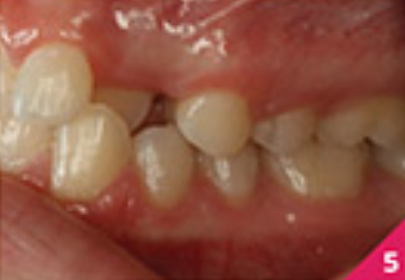

Праве ікло верхньої щелепи було в перехресному перекритті, а різці верхньої і нижньої щелепи були нахилені. Скупчення зубів було помірним у верхньому зубному ряді та легким у нижньому.

На фото зображено розташування зубів перед початком лікування.